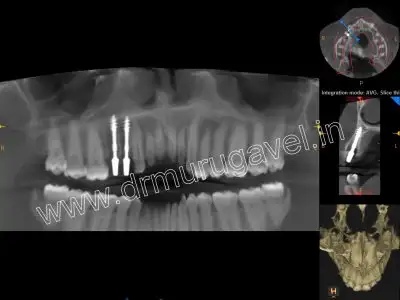

post-implant CBCT image

- OPG and CBCT taken.

- CBCT shows periodontal widening and gp short of apex in relation to 24 region..

- Sufficient bone height and width was present in relation to 24 and 25 region to place implants..

- Extraction of 24 and 25 done and 2 implants placed.